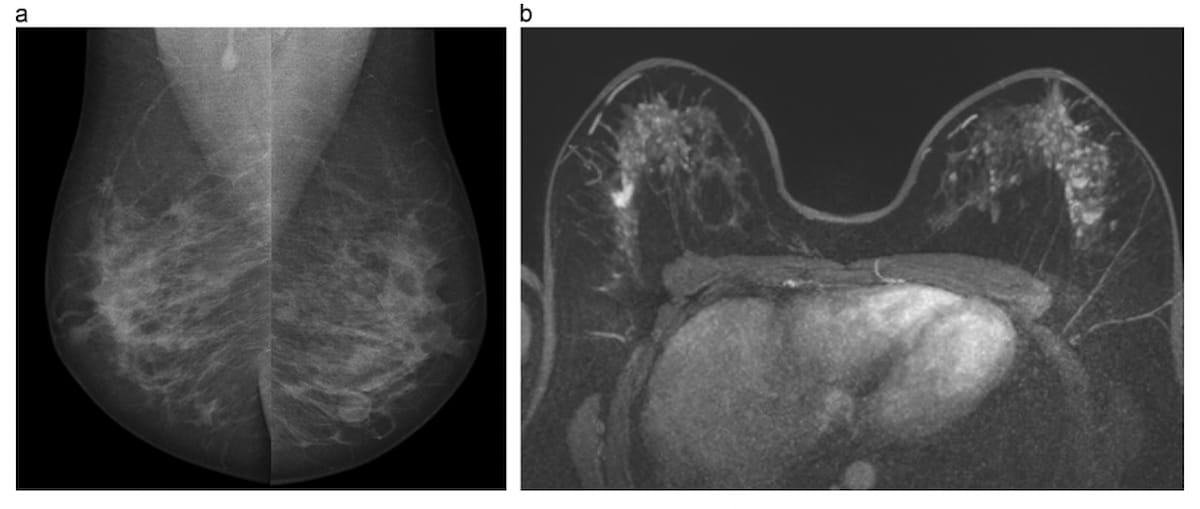

Findings from a new pilot study showed that low-dose positron emission mammography (PEM) detected 96 percent of malignant index lesions and had a 46 percent lower false-positive rate in comparison to breast MRI.